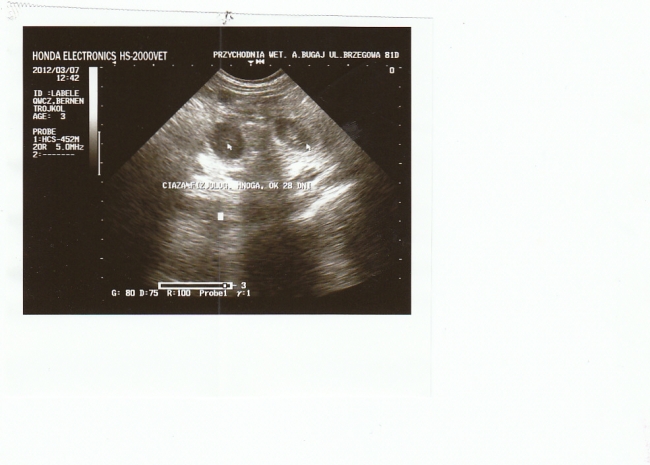

Obrazek został zmniejszony.